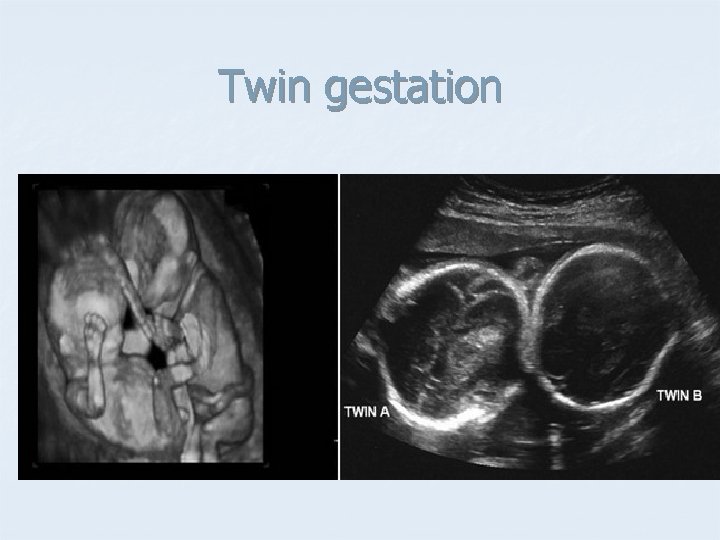

Twin gestation